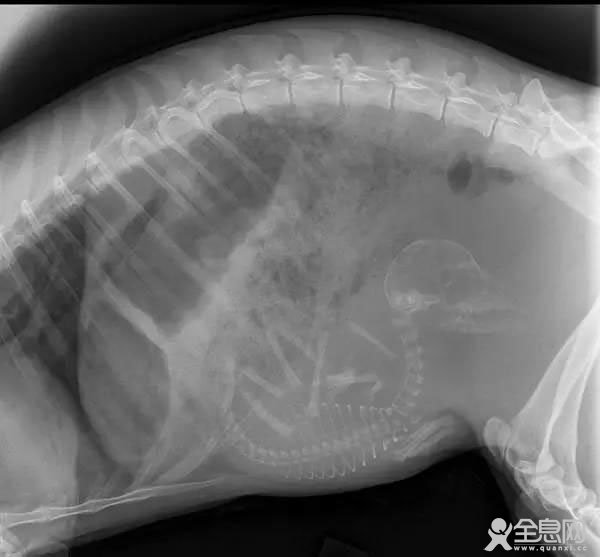

怀孕的蝙蝠。貌似只怀了一个,对么?也是,怀孕的蝙蝠也得飞呀,承不了那么多重量……